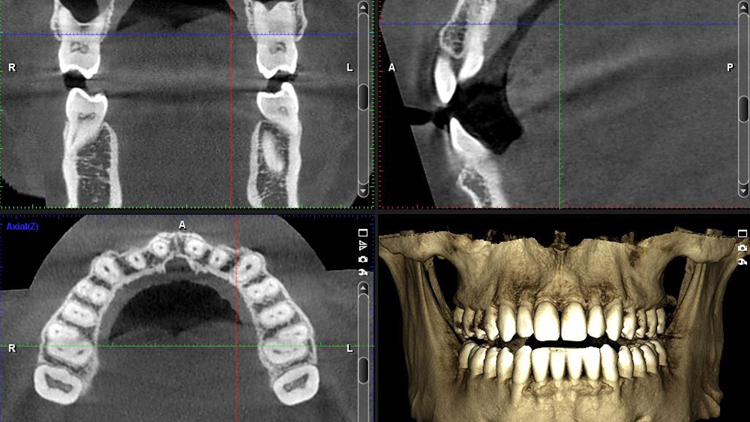

3D Tomografi Nedir?

3D tomografi, diş hekimliğinde kullanılan en gelişmiş görüntüleme yöntemlerinden biridir. Geleneksel röntgenlerden farklı olarak, diş, çene ve yüz yapısını üç boyutlu şekilde gösterir. Bu sayede en ince ayrıntılar dahi görülebilir ve tedavi planlamasında hatasız sonuçlar elde edilir. Özellikle implant cerrahisi, çene eklem sorunları ve gömülü dişlerin konumlandırılması gibi durumlarda büyük avantaj sağlar.

3D Tomografi Nasıl Çekilir?

Hastanın başı özel bir cihazın içine yerleştirilir ve cihaz çene etrafında döner. Çekim sırasında hasta yalnızca 10–15 saniye hareketsiz durur. İşlem tamamen ağrısızdır ve bitiminde görüntüler hemen bilgisayara aktarılır. Böylece diş hekimi sonuçları anında inceleyebilir.

3D Tomografi Sonrası Tedavi Planı

Alınan görüntüler sayesinde diş hekimi, hastanın tedavi sürecini kişiye özel olarak planlar.

- İmplant konumu ve açısı hatasız belirlenir.

- Gerekiyorsa kemik grefti ihtiyacı önceden saptanır.

Çene eklem rahatsızlıklarında en uygun cerrahi yaklaşım seçilir.